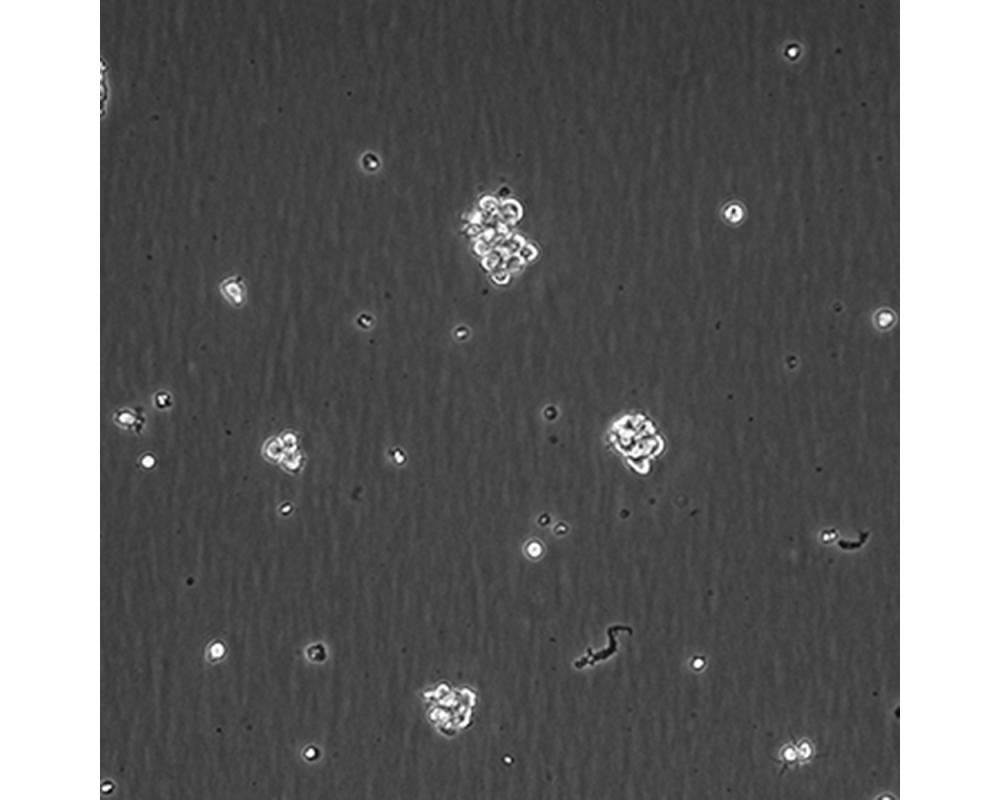

產品名稱 SU-DHL-2

中文名稱 人間變性大細胞淋巴瘤細胞

組織來源 間變性大細胞淋巴瘤;胸腔積液轉移;女性

生長特性 懸浮

培養基 1640,90%;FBS,10%;雙抗。

傳代方法 Maintain cultures at a cell concentraion between between 1 X 10(5) and 1 X 10(6) viable cells/ml.

培養條件 Atmosphere: Air, 95%; CO2, 5%。Temperature: 37℃